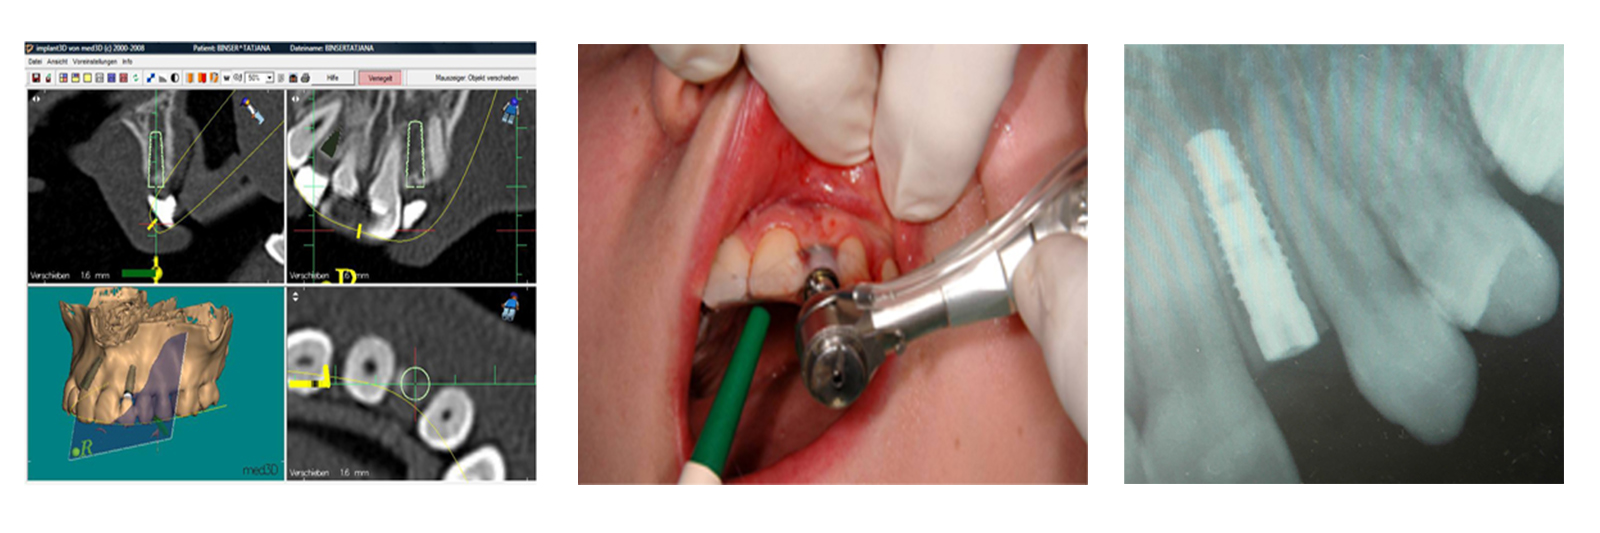

Vorbereitung: Scanschablone, mit der ein CT- bzw. DVT-Datensatz erstellt wird.

3D-Planung am Computer:

Mithilfe unserer Planungssoftware (CeHa-imPLANT) wird die optimale Implantatposition (Richtung und Tiefe des Implantats unter Berücksichtigung der Nachbarzähne/-wurzeln) ermittelt und eine Bohrschablone angefertigt.

Geführte Bohrung mit Tiefenanschlag.